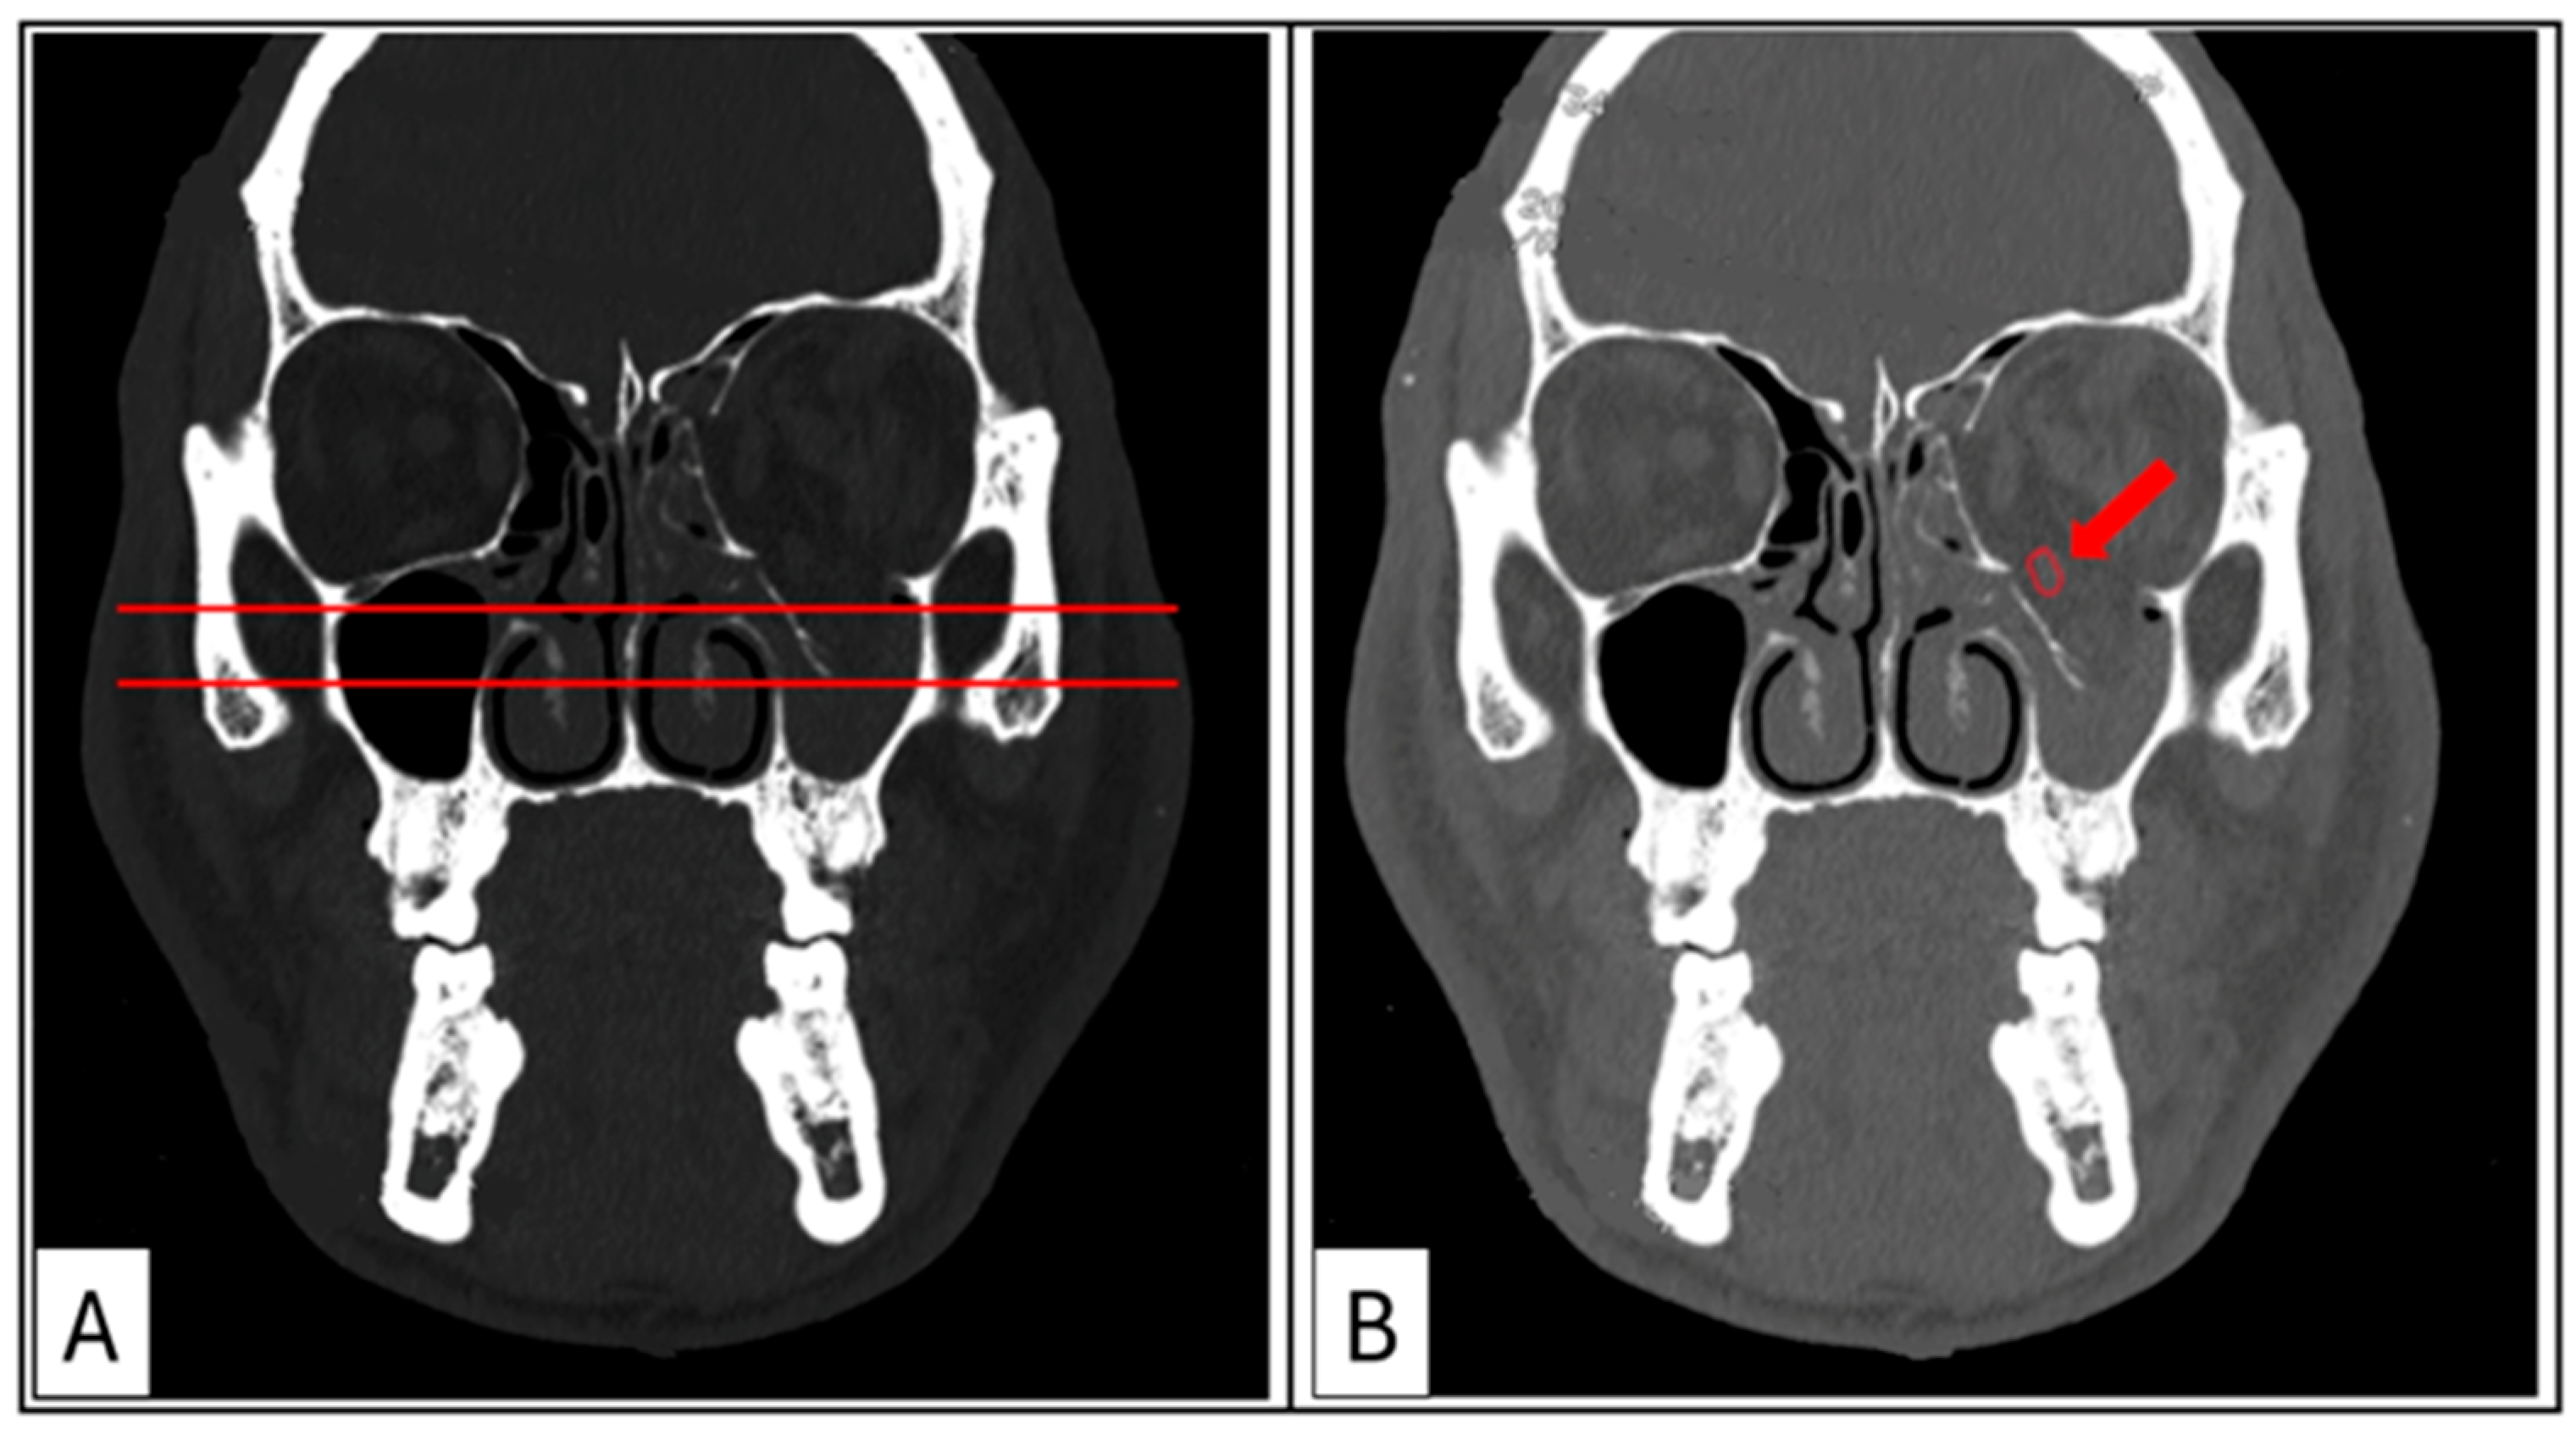

Coronal sections (hard- and soft-tissue windows): These provide the most comprehensive visualisation of the orbit, enabling the assessment of the maximal depression point in comparison to the contralateral side and the status of the ocular muscles (Figure 4A,B). The transition zone (TZ) and lateral wall suture (LW) are identified to establish the mid-orbital rim (MR). The maximum width of the orbital floor fracture and/or the maximum height of the medial wall defect is measured and recorded.

Figure 4. Case 3: Coronal sections. (A) Hard-tissue window for the evaluation of the maximal depression point of the orbital floor compared with the contralateral side. (B) Soft-tissue window showing rounding of the inferior rectus muscle (red arrow), rupture of the periorbita, and tissue herniation into the maxillary sinus.